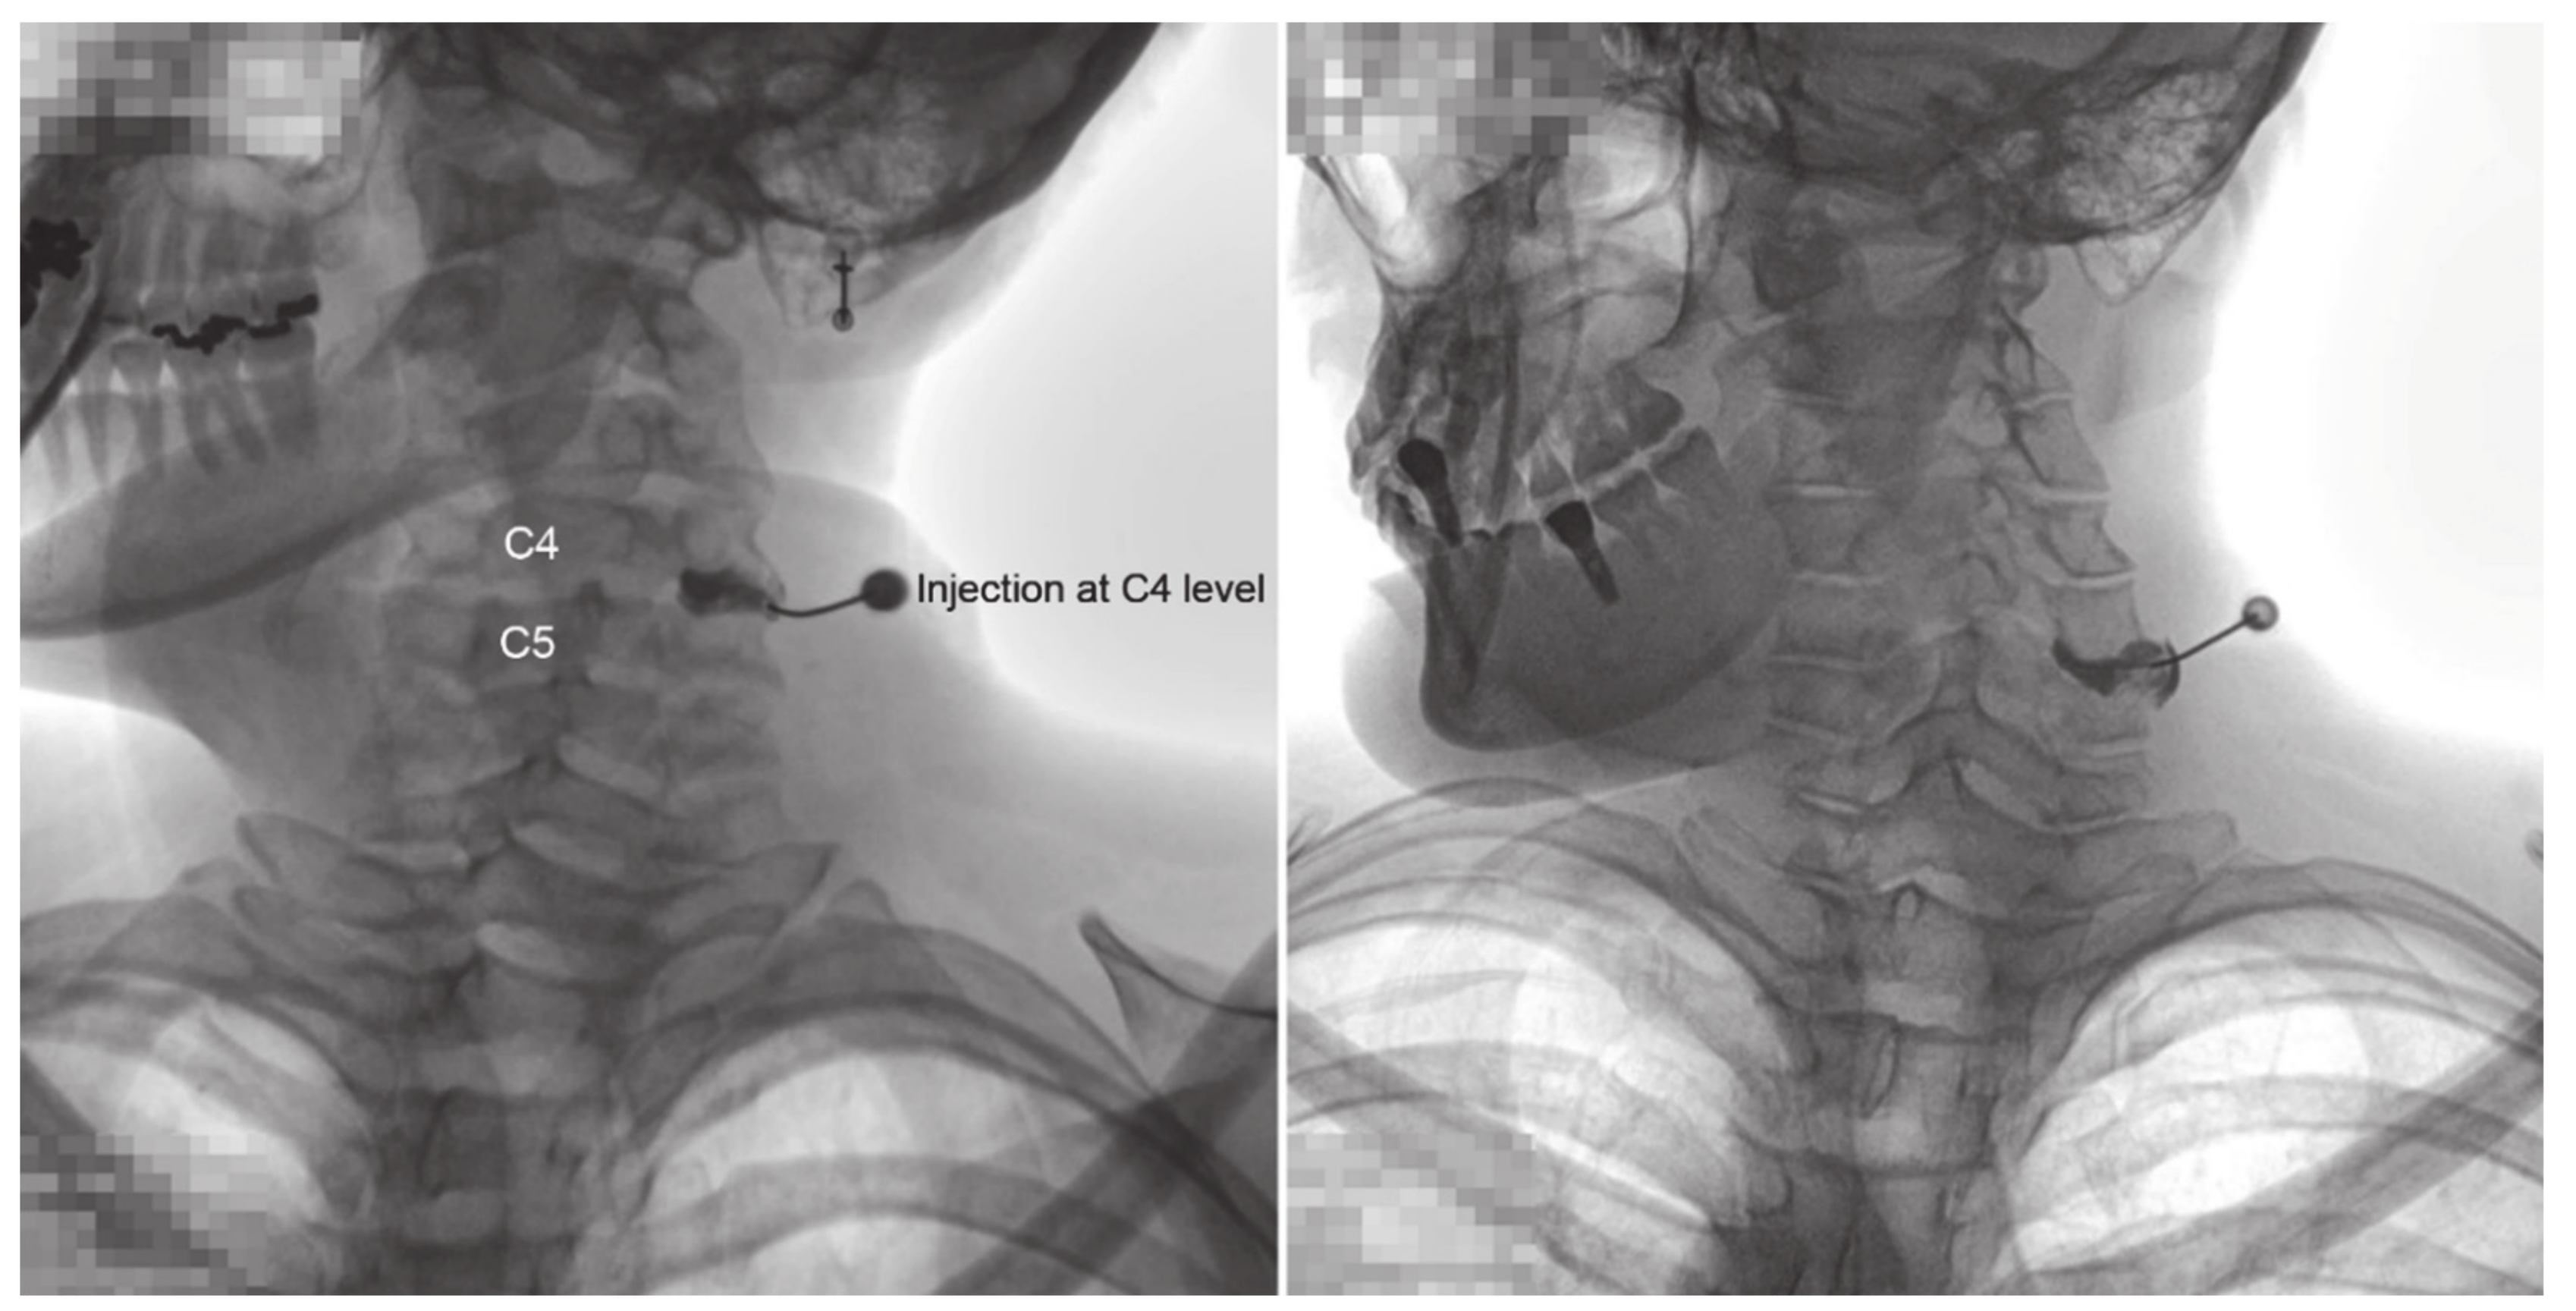

Fluoroscopic Findings of Extra-Cervical Facet Joint Flow and Its Incidence on Cervical Facet Joint Arthrograms

2.2. CFJ Injections/Arthrogram Analyses

3. Results